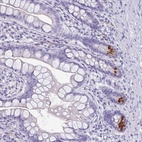

Immunohistochemical staining of human small intestine shows strong cytoplasmic positivity in Paneth cells.